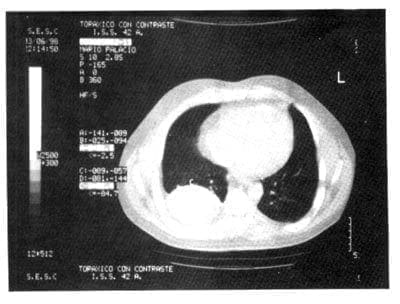

Paraclínicos: Hb: 12.3 gr/L, Hcto: 48% Leucocitos 11.200/mm3 (N: 58% L: 42%), Plaquetas: 430.000 VSG: 47 mm en 1 hora, Glicemia: 78 mg/dl, UN: 12 mg/dl, Creatinina: 1mg/dl, Factor Reumatoideo: 1/40 PCR: 12 mg/L Rx Tórax: Presencia de radio-opacidad en base hemitórax derecho correspondiente a masa de localización pleural (Figura 1). TAC de Tórax: masa redondeada de 8 cm de diámetro, ubicada en el espacio pleural derecho en su parte inferior (Figura 2).

TAC de Tórax: Se evidencia masa redondeada de 8 cm de diámetro, ubicada en el espacio pleural derecho, parte inferiorFigura 2: TAC de Tórax: Se evidencia masa redondeada de 8 cm de diámetro, ubicada en el espacio pleural derecho, parte inferior.